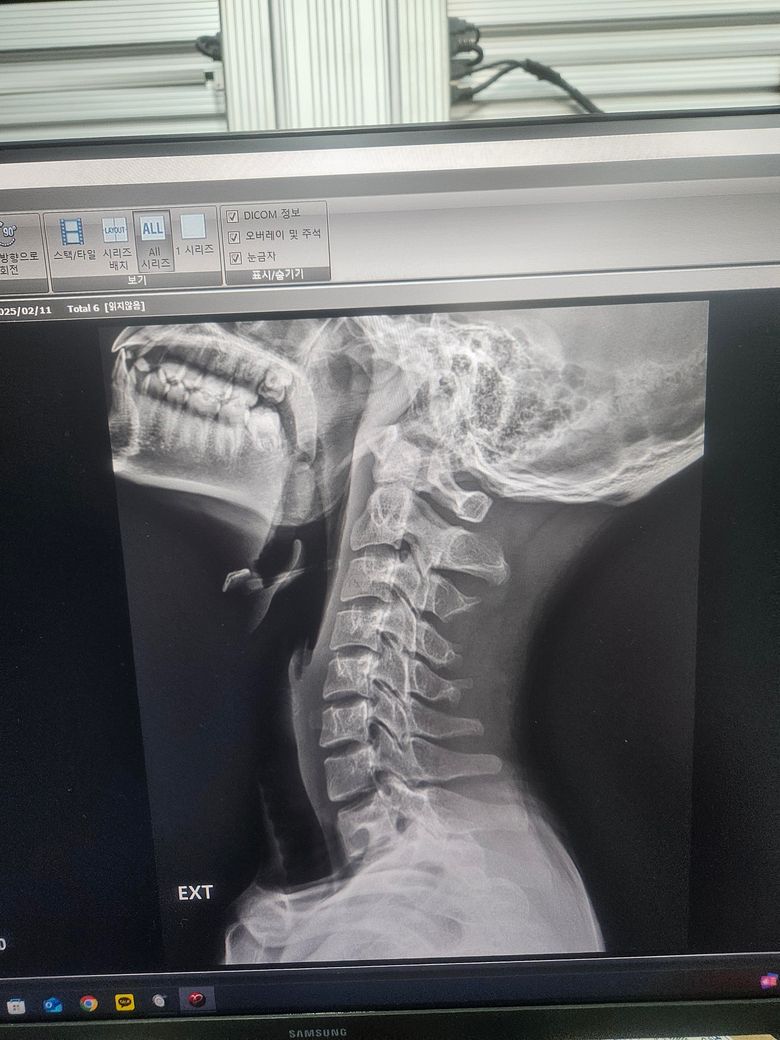

신전 시 상부경추의 움직임 줄어들어 있는 상태이며 하부경추에서 5, 6번 움직임이 증가되는 것 같습니다.

경추는 1, 2, 3번이 상부 경추 4, 5, 6, 7번이 하부경추로 나눠지며

움직임 역시 상부경추는 움직임 ↑, 하부경추는 안정성 ↑